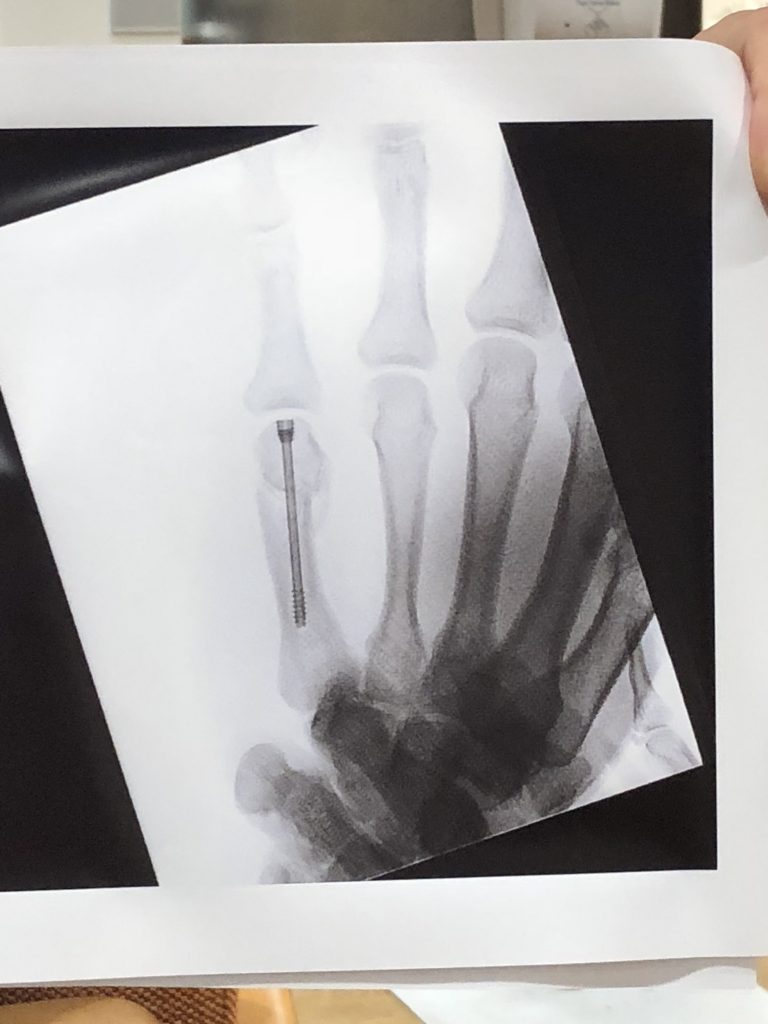

Senior year in high school for Ryan was sure to be an exciting one! A Varsity starter for an undefeated NJ football team and a key player on the Varsity basketball team. With a 4.0 GPA, Ryan was all set for his final year in high school. But during the first weeks of football preseason, Ryan collided with a teammate, fracturing a bone in his right hand. After rushing him to a walk-in urgent care for an x-ray, the doctor consoled him saying “your season is over before it even started”. It was a Thursday night and it was one of the few times I saw Ryan get emotional. He looked defeated. The next morning I called HSS. My mom had both hips replaced and a knee replaced by Dr Mark Figgie. I knew if Ryan was going to see the field his senior year that HSS was my best shot. I called the central number and was immediately put through to Dr Fufa’s office. Although she was out of town, they assured me that a resident doctor could evaluate Ryan for Dr. Fufa and get the ball rolling should he need surgery. Dr. Fu (Chief Resident) told us Ryan had a “boxer's fracture” and would need surgery for the hand to heal properly. By chance there was a cancellation and the surgery was scheduled 4 days later. This Saturday, just 30 days after surgery Ryan will play football! With a special “club cast” in place for 2 games, he was cleared to play without restriction. We are so thankful to the HSS team for getting Ryan back to his team! HSS is simply the best in orthopedics!